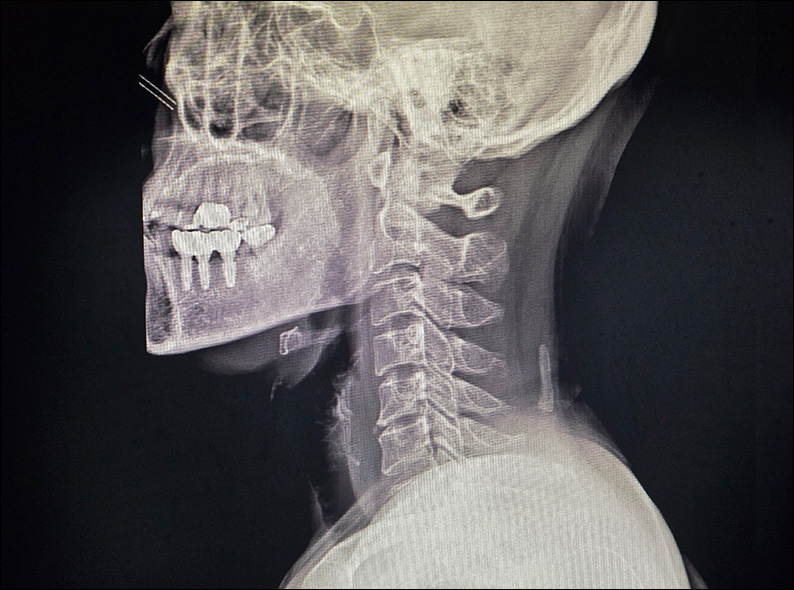

거북목, 목디스크, 협착증, 후관절증후군 등 경추질환에 의한

뒷목, 어깨, 팔, 손의 통증과 감각이상도 검증된 비수술치료로 호전될 수 있습니다.

목덜미 통증으로 물리치료와 도수치료를 받았으나 악화되어

어깨와 팔의 방사통과 손 저림까지 발생한 환자.

경추의 C자형 커브가 일자로 변형되고 뼈의 퇴행성 변화도 관찰되는 상태